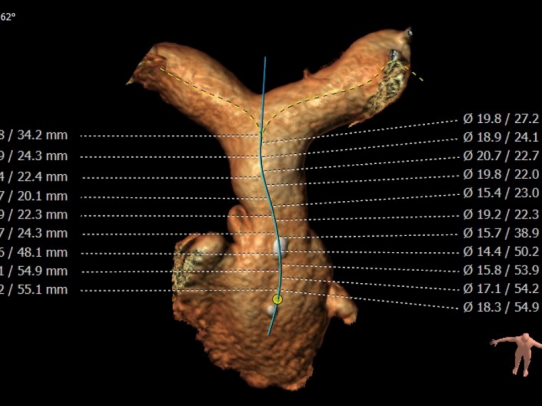

CT重建肺动脉

主肺动脉腰部截面